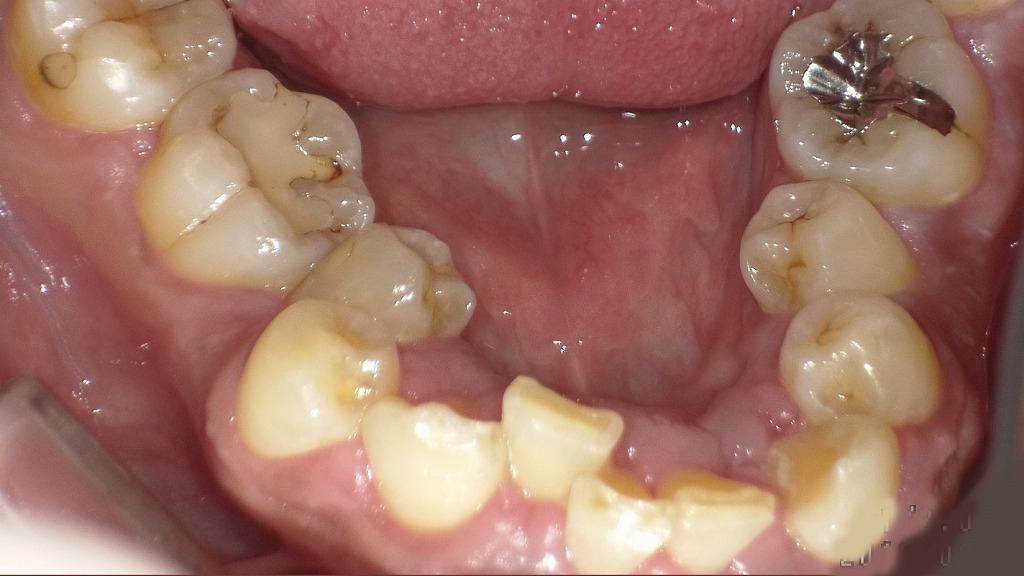

子供の下の前歯がガタガタの症例

この画像は、6歳児の下顎前歯部(永久歯の萌出期)を示しています。専門的に解説すると以下のようになります。

🔍 状況の概要

赤い矢印の部分に見られるように、**下顎の永久歯(中切歯:1番)が2本とも萌出を開始しています。しかし、乳歯列に隙間(歯間空隙)がなく、萌出スペースが不足しているため、永久歯がガタガタ(叢生)**の状態で生えてきています。

🦷 詳細な所見

- 永久歯の萌出位置

下顎中切歯(1番)は乳歯の裏側(舌側)から萌出しています。これは6歳前後ではよく見られる生理的な現象で、「舌側萌出」と呼ばれます。

通常は後に乳歯が自然に脱落し、舌の圧で永久歯が前方へ移動し、正しい位置に落ち着くこともあります。 - スペース不足の原因

この症例では乳歯列の歯間に隙間がほとんどなく、もともと顎の成長や歯列弓の幅が狭いタイプです。

そのため、永久歯が生えるスペースが足りず、**前歯の叢生(ガタつき)**を生じています。 - 今後の注意点

永久歯の萌出が進む6~8歳の時期に、乳歯の自然脱落と顎の成長によってある程度改善するケースもありますが、

スペースが極端に不足している場合や、側方歯(側切歯・犬歯)の萌出時に重なりが強くなるリスクが高いです。

その場合は、早期矯正(咬合誘導)や顎の成長を促す装置の検討が望まれます。

📋 まとめ

| 項目 | 内容 |

|---|---|

| 年齢 | 約6歳 |

| 状況 | 下顎永久中切歯の舌側萌出+叢生傾向 |

| 問題点 | 乳歯列に隙間がないため萌出スペース不足 |

| 今後の対応 | 乳歯の自然脱落を経過観察し、必要に応じて矯正相談へ |

この時期の診断ポイントは、乳歯が抜けた後に前歯が並ぶ余地があるかどうかです。もし隙間が全くないまま永久歯がずれて生えてくる場合、早期に矯正的介入を検討することが将来的な歯列不正の予防につながります。